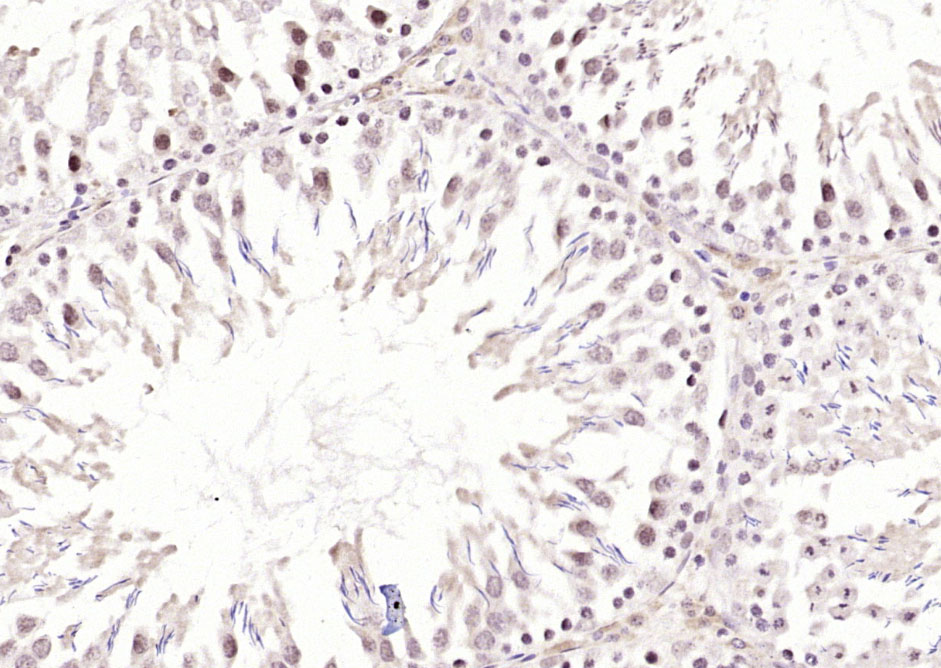

Paraformaldehyde-fixed, paraffin embedded (rat testis); Antigen retrieval by boiling in sodium citrate buffer (pH6.0) for 15min; Block endogenous peroxidase by 3% hydrogen peroxide for 20 minutes; Blocking buffer (normal goat serum) at 37°C for 30min; Antibody incubation with (Ube2N) Polyclonal Antibody, Unconjugated (bs-8351R) at 1:200 overnight at 4°C, followed by operating according to SP Kit(Rabbit) (sp-0023) instructionsand DAB staining.